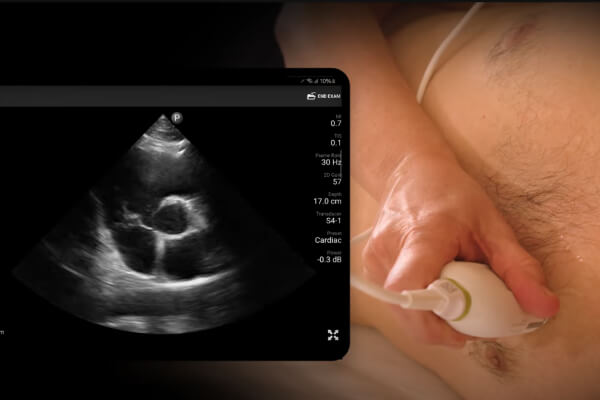

AP4 View

Learn how to obtain the apical 4th chamber view